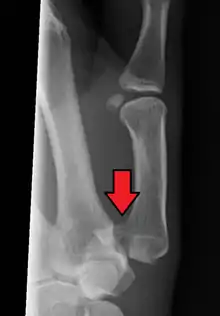

Bennett fracture is a type of partial broken finger involving the base of the thumb, and extends into the carpometacarpal (CMC) joint.[1]

This intra-articular fracture is the most common type of fracture of the thumb, and is nearly always accompanied by some degree of subluxation or frank dislocation of the carpometacarpal joint.

Though these fractures commonly appear quite subtle or even inconsequential on radiographs, they can result in severe long-term dysfunction of the hand if left untreated. In his original description of this type of fracture in 1882, Bennett stressed the need for early diagnosis and treatment in order to prevent loss of function of the thumb CMC joint, which is critical to the overall function of the hand.[4]